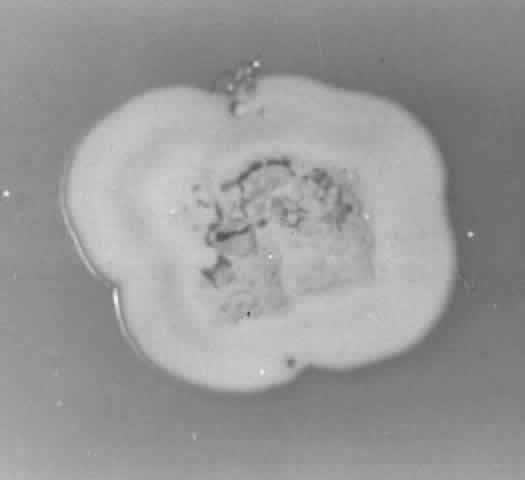

Growth occurs on Sabourauddextrose agar without antibiotics, Lowenstein-Jensen medium, and Middlebrook 7H11 agar and matures within 7 to 9 days. Colonies on Sabouraud dextrose agar are white to orange, raised, irregular or smooth (Fig. 9). Microscopically on tap water agar are seen thin, delicate, branching, beaded filaments that fragment into bacillary or coccoid forms (Fig. 10). They are gram positive and may be partially acid fast. There are three major pathogens to humans: N. asteroides, N. brasiliensis, and N. otitidiscaviarum.

Fig. 9. Colony of Nocardia asteroides on Sabouraud dextrose agar.